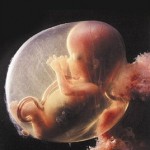

Bebeğiniz, hamileliğin en kritik dönemlerinden birini geride bırakmaya hazırlanıyor. Bu hafta itibariyle bütün hayati organları oluşmuş ve işlevlerini yerine getirmeye başlamaya hazırdır. Ancak bu organlar hamilelik boyunca gelişimlerine devam edecektir.

En hızlı gelişen organ beynidir, bu nedenle bu haftalarda bebeğinizin kafası vücuduna oranla oldukça büyüktür. Gözlerinin iris tabakası oluşmaya başlamış olsa da, göz kapakları henüz açık değildir. Aynı zamanda bacak ve kolları daha belirgin hale gelir ve eklemleri hareket etmeye başlar.

Bebeğinizin kemik ve diş gelişimi de bu dönemde başlar, bu nedenle yeterli miktarda kalsiyum almak oldukça önemlidir. Beslenme listenize süt, yoğurt, peynir ve yeşil yapraklı sebzeleri dahil etmeyi unutmayın.